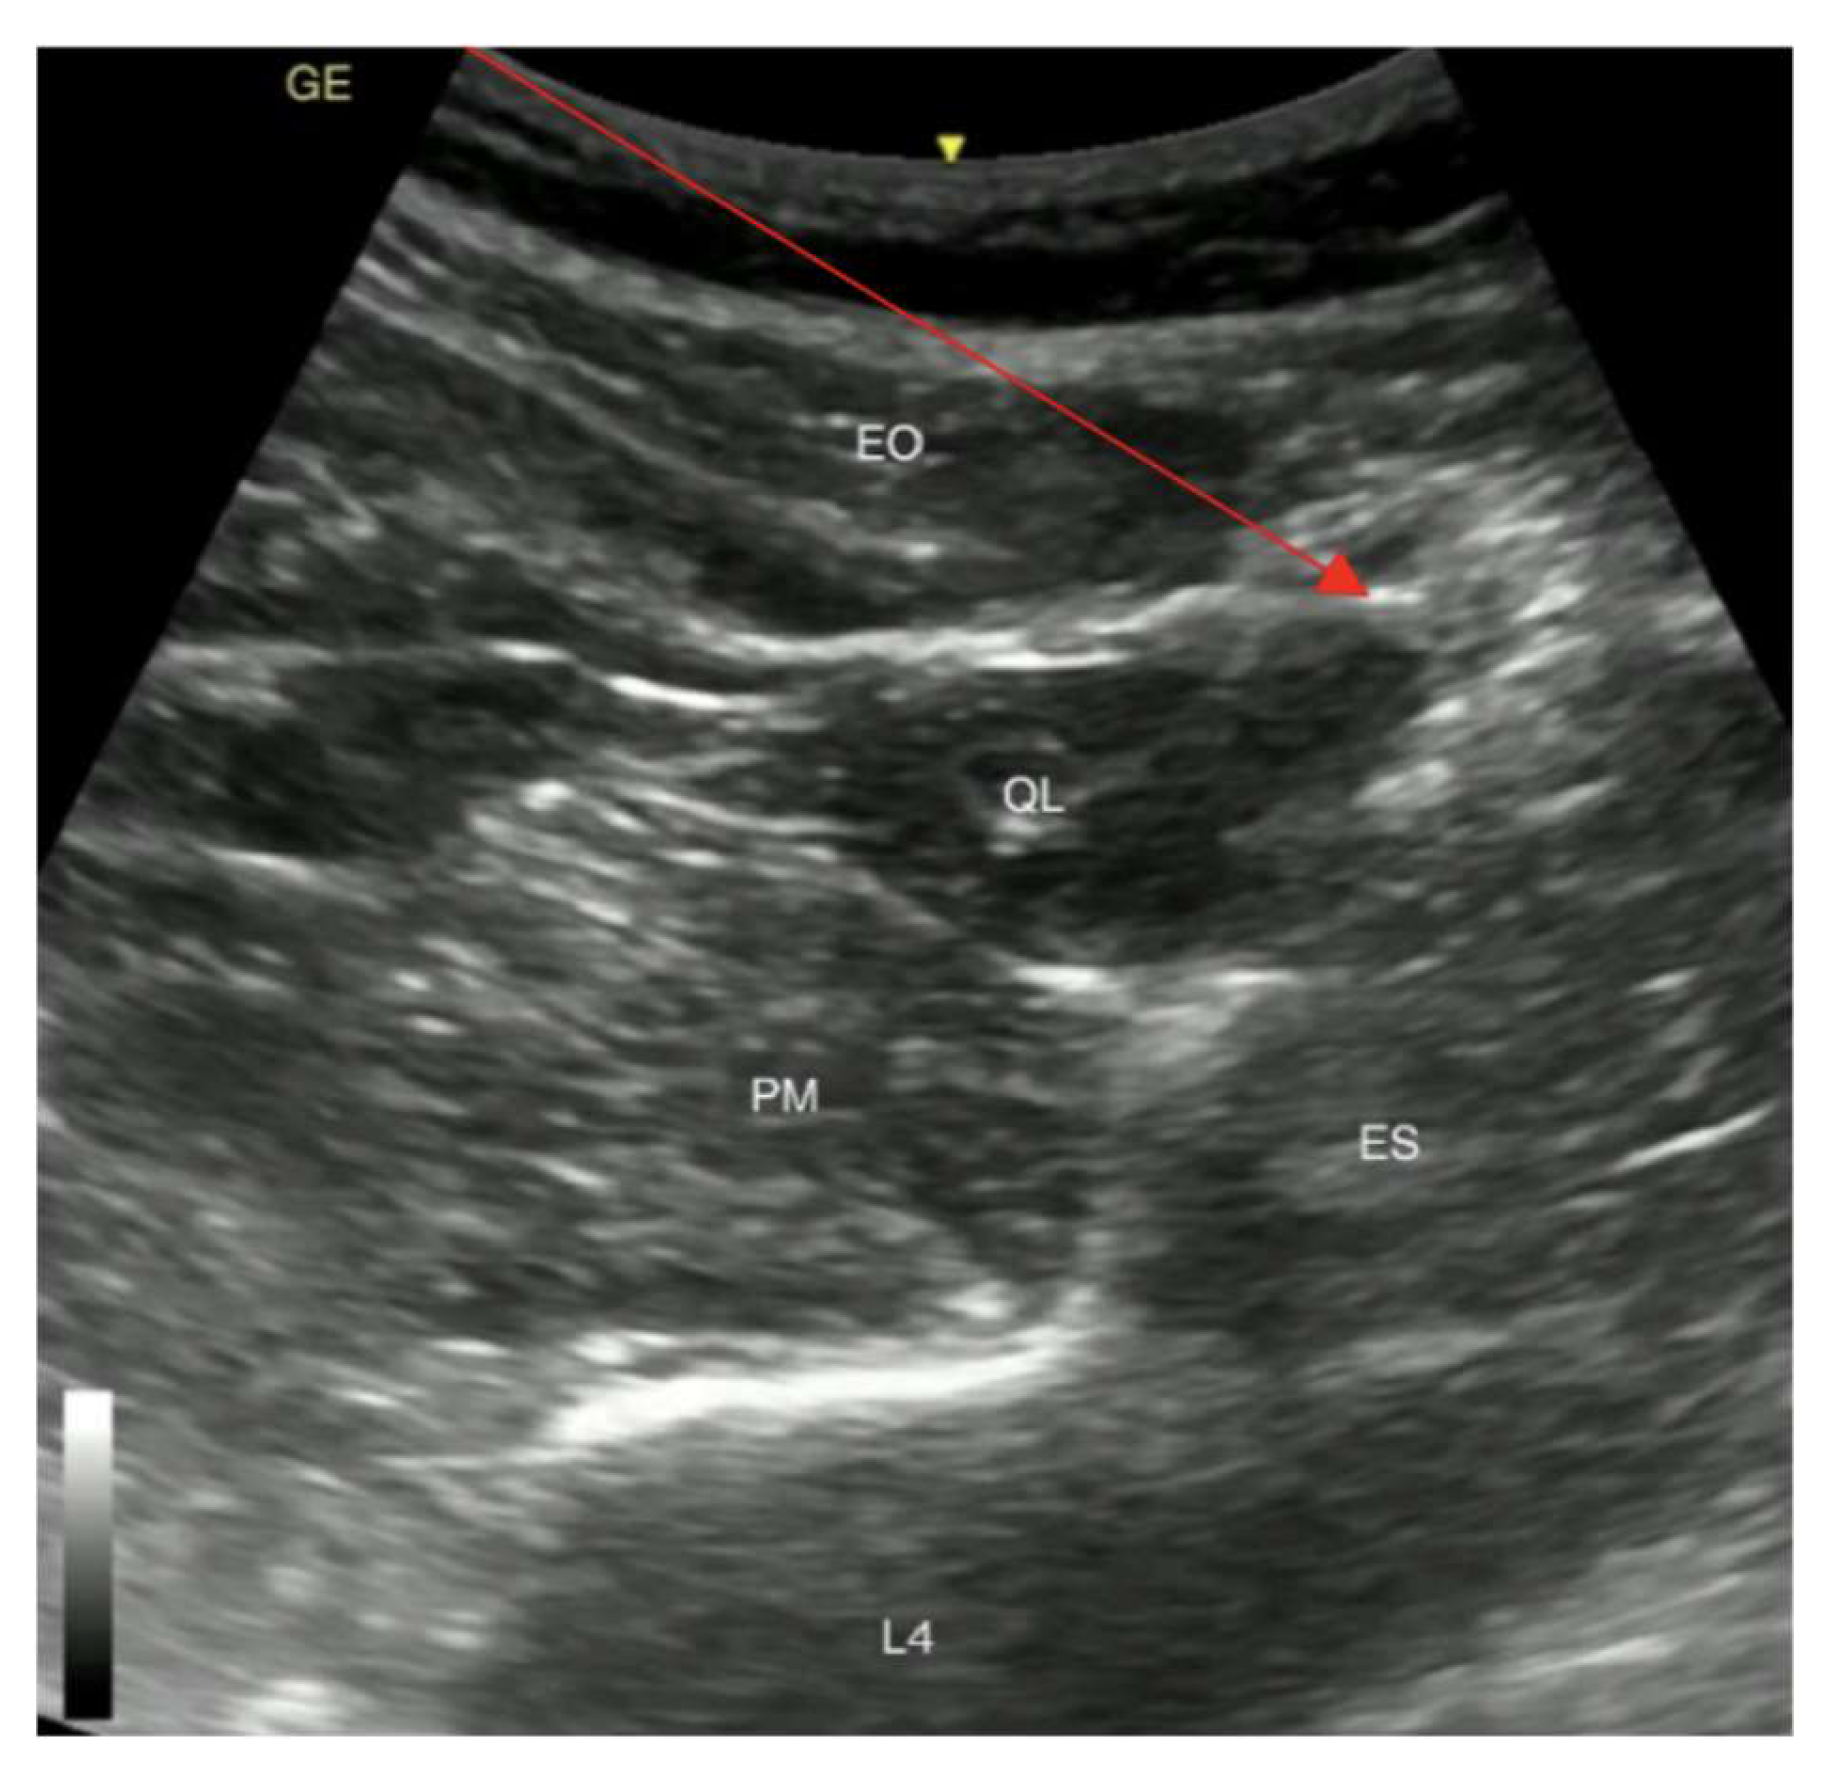

The procedure was stopped because of the patient’s airway obstruction caused by the hypopharynx carcinoma, followed by a desaturation of SpO2 to 23% when 50 mg propofol was administered (1.2 mg/kg intravenous propofol). Following these dramatic complications, the patient was given intravenous Sol. Dexoni 8 mg and O2 lung ventilation with an Ambu bag was performed. The patient’s oxygen saturation returned to 86–92% after 6 min. As her oxygen saturation at rest was within the normal range, there were no indications for tracheostomy. After experiencing complications associated with anaesthetics and considering the possible risk with patient intubation and further desaturation, the decision for the placement of a gastrostomy tube was made in the operating room and the anaesthesia of choice was the quadratus lumborum block type 2 (QLB2) (Figure 3).

Figure 3. Posterior QLB (type 2). EO, external oblique muscle; QL, quadratus lumborum muscle; PM, psoas major muscle; ES, erectores spinae muscle; L4, fourth lumbar vertebra; Red arrow shows the needle path for posterior QLB. The yellow arrow shows patient’s skin.